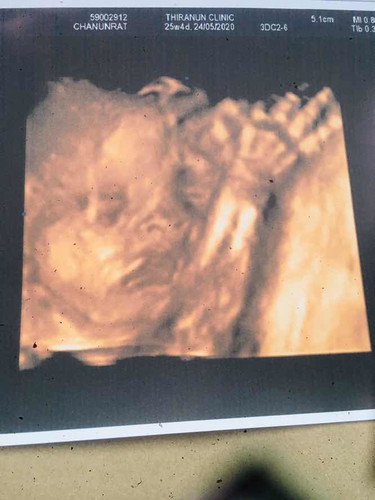

แค่หนูสมบูรณ์ แม่ก็ดีใจที่สุดแล้วครับคนเก่งของแม่ ทีมพค 63ค่า??